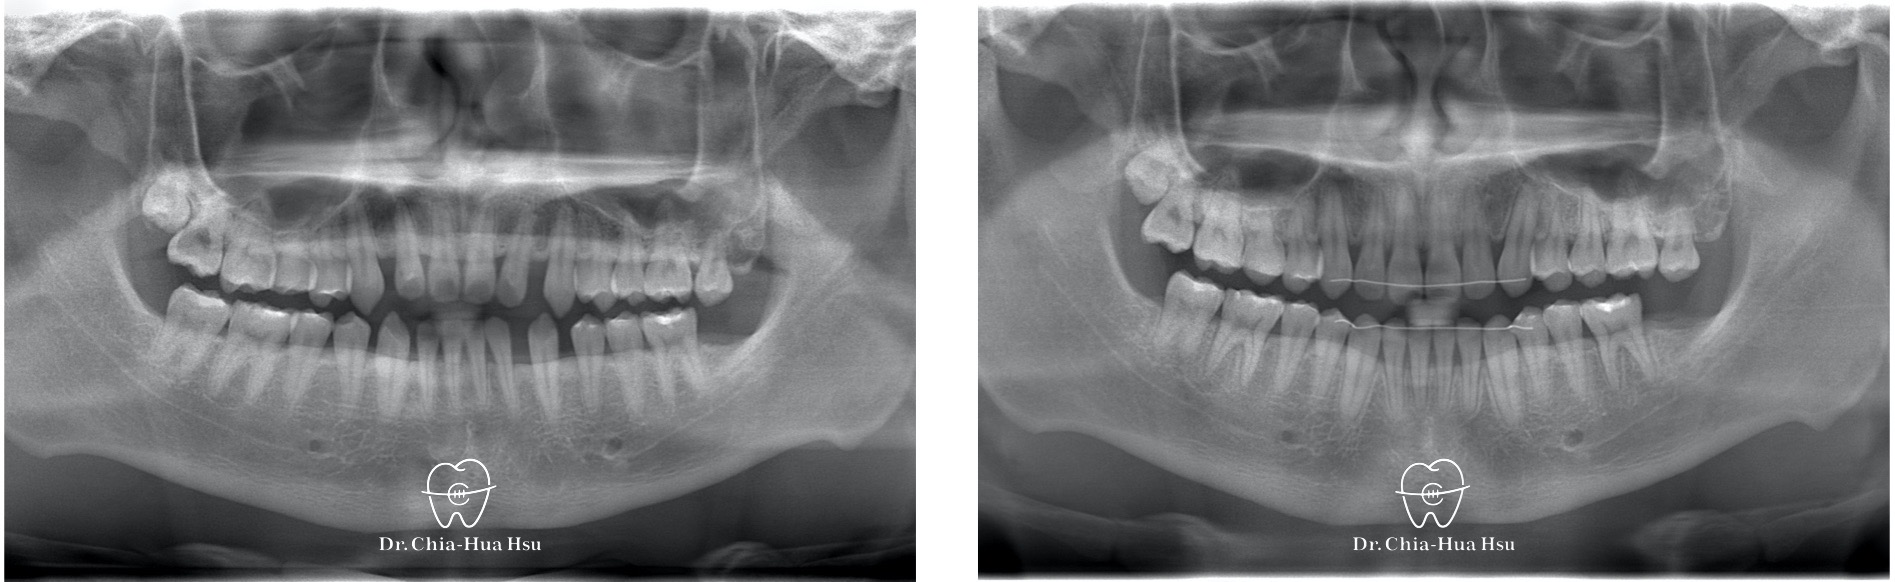

治療前

治療後